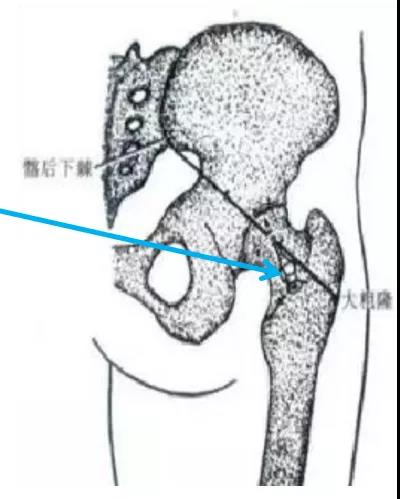

后路进针法:患者俯卧位,或侧卧位,患侧在上。在大粗隆中点与髂后下棘连线的中、外1/3交界处为穿刺点。常规消毒铺巾,用7号长穿刺针垂直或稍向上刺入,至骨面后稍退针,此时针尖在关节腔内。